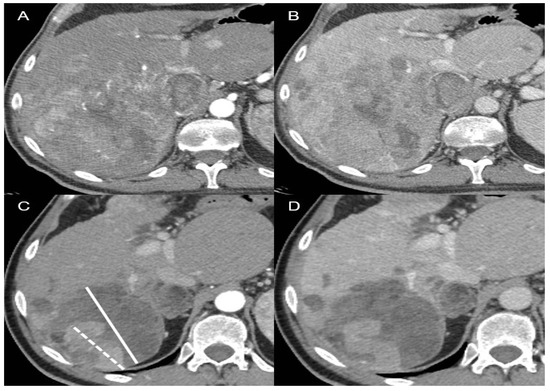

- Lencioni, R.; Llovet, J.M. Modified RECIST (mRECIST) assessment for hepatocellular carcinoma. Semin Liver Dis. 2010, 30, 52–60. [Google Scholar] [CrossRef] [PubMed]

- Llovet, J.M.; Lencioni, R. mRECIST for HCC: Performance and novel refinements. J. Hepatol. 2020, 72, 288–306. [Google Scholar] [CrossRef] [PubMed]